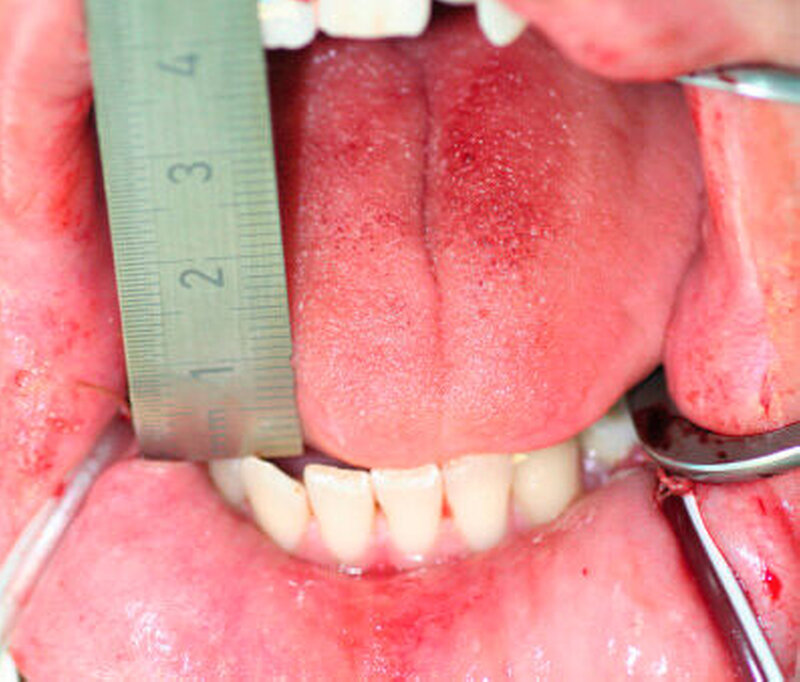

Im Rahmen des Gesprächs berichtete der Patient über eine schmerzfreie, jedoch eingeschränkte Mundöffnung, die er bisher aber nicht hatte untersuchen lassen. Die spezielle Anamnese lieferte keine Hinweise für eine mögliche Ursache der eingeschränkten Mundöffnung. Während der klinischen Untersuchung konnte eine Mundöffnung von 20 mm (SKD) gemessen werden (Abbildung 1).